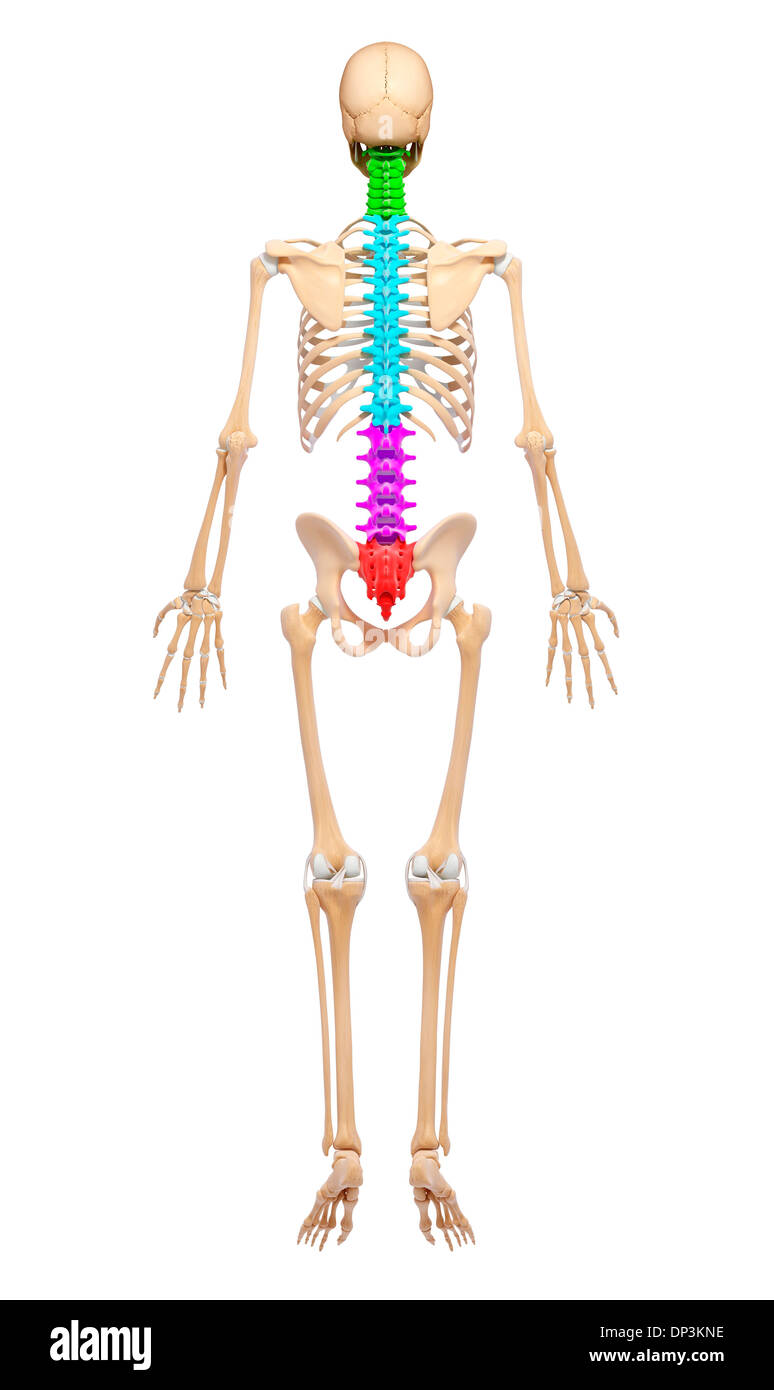

Human Skeleton, artwork Banque D'Imageshttps://www.alamyimages.fr/image-license-details/?v=1https://www.alamyimages.fr/human-skeleton-artwork-image65234890.html

Human Skeleton, artwork Banque D'Imageshttps://www.alamyimages.fr/image-license-details/?v=1https://www.alamyimages.fr/human-skeleton-artwork-image65234890.htmlRFDP3KNE–Human Skeleton, artwork